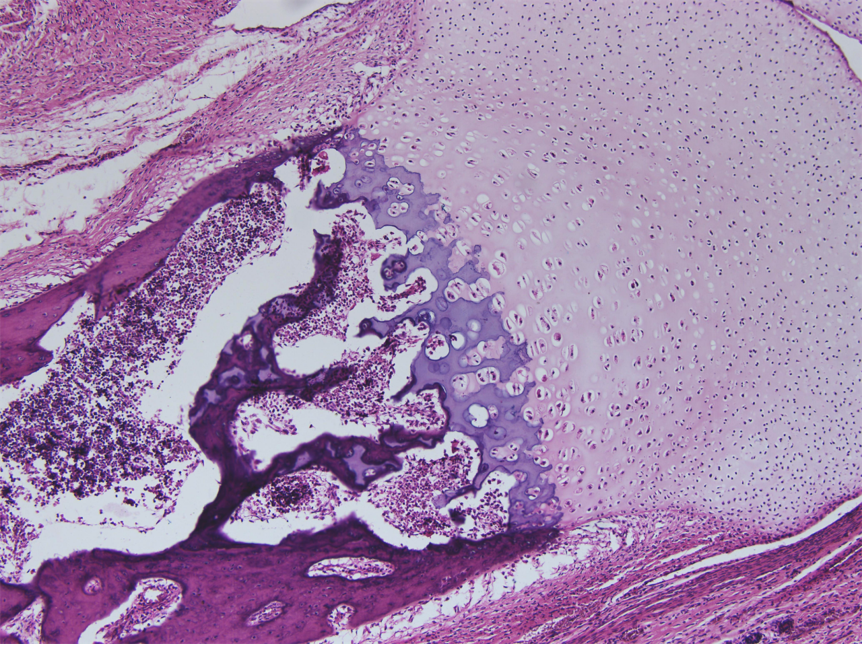

透明软骨(hyaline cartilage)分布较广,成体的关节软骨、肋软骨及呼吸道的一些软骨均属这种软骨。新鲜时呈半透明状,较脆,易折断。透明软骨间质中的纤维为胶原原纤维,含量较少,基质较丰富。

(1)软骨细胞(chondrocyte):位于软骨基质内的小腔――软骨陷窝(cartilage lacuna)中。陷窝周围有一层含硫酸软骨素较多的基质,称软骨囊(cartilage capsule),染色时呈强嗜碱性。软骨细胞在软骨内的分布有一定规律,靠近软骨膜的软骨细胞较幼稚,体积小,呈扁圆形,单个分布;位于软骨中部的软骨细胞接近圆形,成群分布,每群有2~8个细胞,它们是由一个细胞分裂增生而成,故称同源细胞群(isogenous group)。同源细胞群中的细胞分别围以软骨囊。软骨细胞核呈椭圆形,细胞质弱嗜碱性。新鲜软骨的软骨细胞充满于软骨陷窝内。但在HE染色切片中,细胞收缩成不规则形,故软骨囊和细胞之间出现较大的空隙。软骨细胞的超微结构特点是胞质内有丰富的粗面内质网和发达的高尔基复合体,还有一些糖原和脂滴,线粒体较少。软骨细胞主要以糖酵解方式获得能量。

(3)纤维:透明软骨中无胶原纤维,但有一些由Ⅱ型胶原组成的胶原原纤维,它们呈交织状分布。胶原原纤维直径为10~20nm,无明显横纹,其折光率与基质相近,故在光镜下不易分辨。软骨囊含硫酸软骨素较多,含胶原原纤维少或无,故嗜碱性较强。软骨囊之间则含胶原原纤维较多,故呈弱嗜酸性。